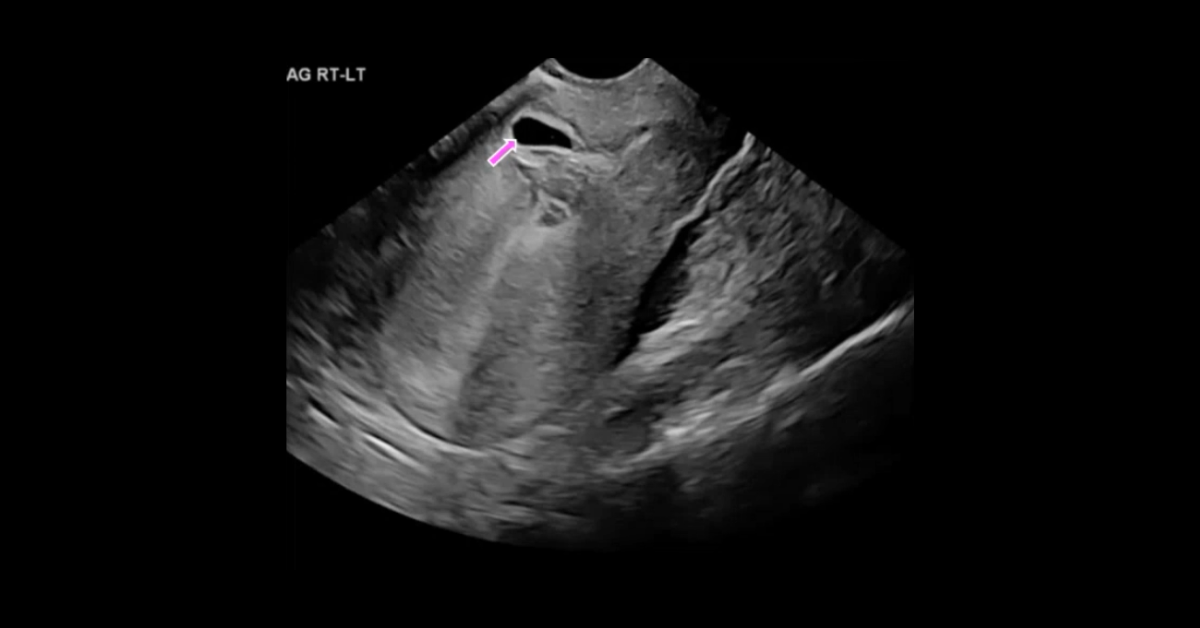

A collection of obstetric ultrasound studies presented in cine and screen shot formats, with initial presentation of each case enabling participants to render their own diagnoses followed by detailed discussion of each case.

1. Describe the typical US findings in a variety of obstetric abnormalities.

2. Understand the appearance of umbilical cord and placental abnormalities.

3. List the clinically relevant abnormalities of the umbilical cord.